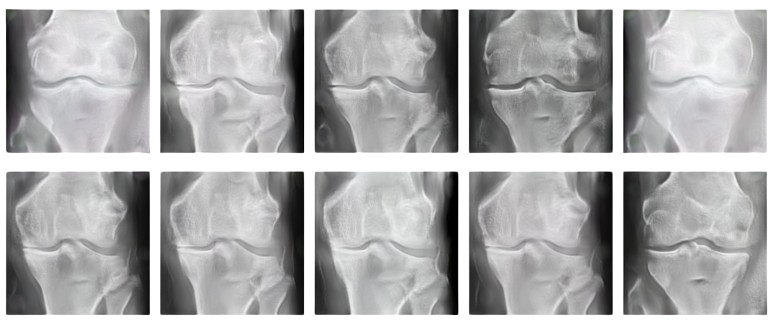

Synthetic Knee Images Generation

Used GANs to generate synthetic knee images with various Kellgren-Lawrence (KL) grades.